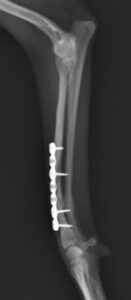

右前腕骨折のポメラニアンちゃんが来院されました。橈尺骨骨折は動物病院では一番よくある骨折です。ロッキングプレートであるTAITAN1.2で対応しました。治りも順調で元気に帰りました。よかったね。